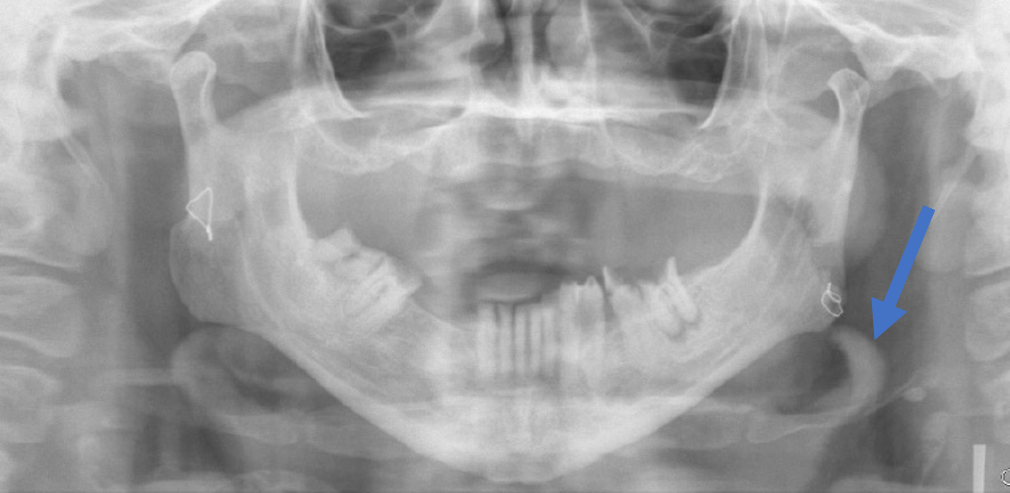

3) Identify the asymptomatic radiopacity indicated by the blue arrow. Patient is 65 years old and suffered from Diabetes and hypertension.

4) In the previous case, would you like to refer the patient to a General Practitioner?